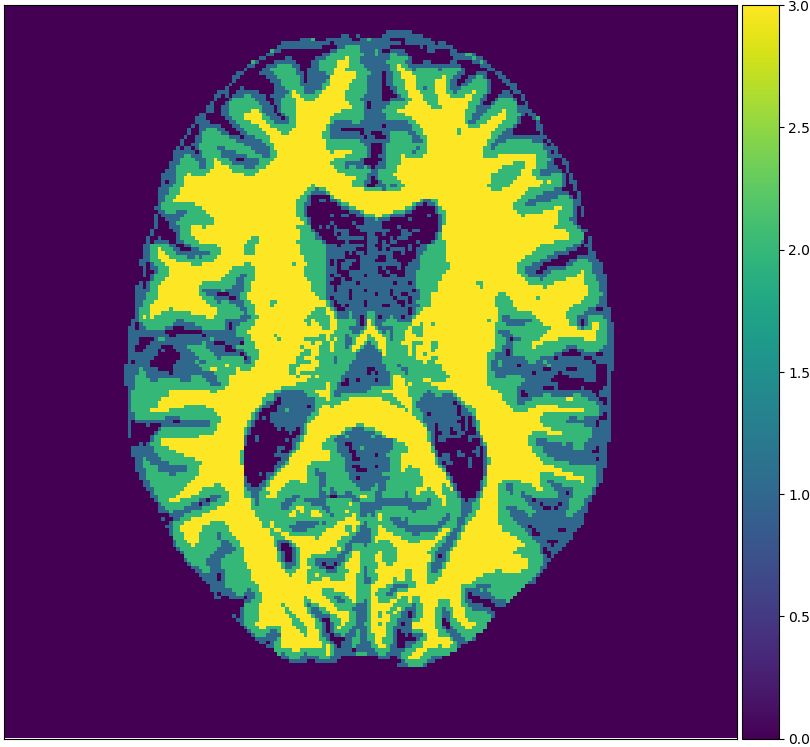

We will make use of 3 publicly available data sets: Brainweb1.5T, MRBrainS13, and IBSR. Each data set originates from one medical center. Brainweb1.5T is based on 20 realistic phantoms from Brainweb [2] and an MRI simulator (SIMRI; [3]). The simulator was set to use TE, TR and flip angle parameters of the 1.5T scanner in the Rotterdam Scan Study [9]. MRBrainS13 is a grand challenge for medical image tissue segmentation methods containing 5 scans for training [14]. The scans are 3T and have been fully manually annotated. IBSR is a classical data set of 18 patients and is automatically segmented but manually corrected [18]. Skulls are stripped off in all scans. Figure 1 visualizes examples from these sets.

Figure 2 shows examples of each segmentation method on the MRBrainS13 data set, with Brainweb1.5T as the source center. For the unsupervised models we only show boundaries between clusters, to indicate that interpretation remains a necessary step. A couple of observations can be made: firstly, the hidden Potts models produce smoother segmentations. Secondly, the U-net over-predicts white matter in the whole image. Thirdly, the 1-nearest-neighbours classifier over-predicts background voxels in fluid regions. Lastly, all methods favour white matter over gray matter in ambiguous regions.